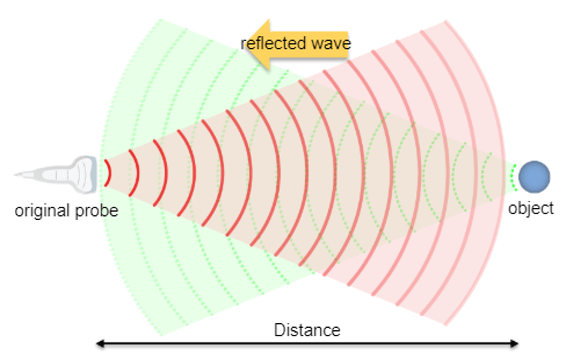

In Ultrasound, the transducer emits high-frequency sound waves. These waves, as they propagate through organs, will be reflected then processed and analyzed to create the image.

However, a sound wave, propagated in the air, will reflect each time it collides with a solid surface. This thoughtful sound is called an echo. The same applies to ultrasonic waves that propagate through organs and run into an obstacle.

An ultrasound probe emits a pulse in response to electrical excitation. This ultrasonic pulse, transmitted to biological tissues, spreads by degrees.

The echoes are generated by reflection or scattering and propagate backward towards the probe, which operates in receiver mode immediately after the pulse is transmitted. Whenever an echo reaches the surface of the probe, an electrical signal is produced, having an amplitude proportional to that of the echo.

If we consider that an ultrasound wave propagates in the soft tissues at a constant mean speed c, the time t (echo flight time) that elapses between the emission and the reception of an echo, corresponds to the duration of a round trip to the target which is expressed simply by the fundamental relationship of ultrasound: ct = 2z, where c is the ultrasound speed, t is the time of propagation, and z is the penetration distance.